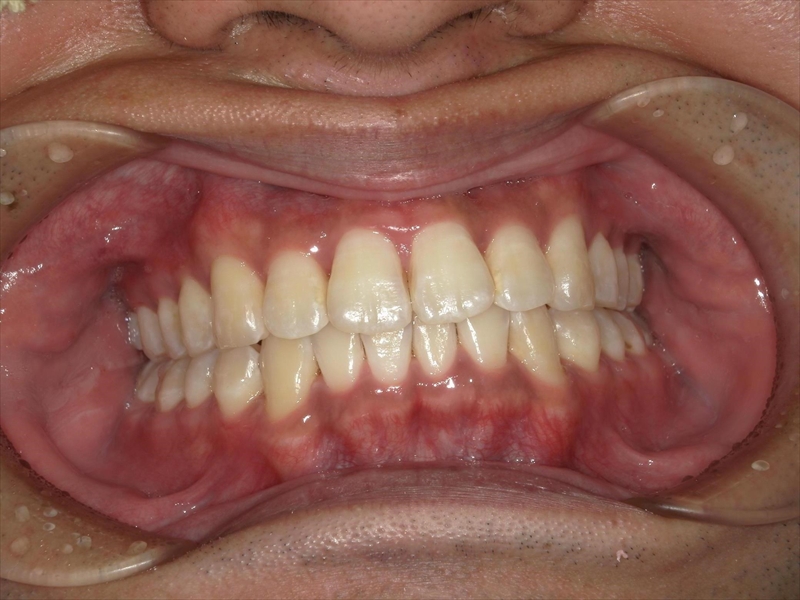

【大人矯正治療例】前歯のV字状の捻じれと出っ歯、叢生、過蓋咬合をインビザラインできれいな歯並びに

患者様の努力(マウスピース装着時間確保、MFT)もあり、きれいに並べることができました。

治療前後 写真

素敵な笑顔に